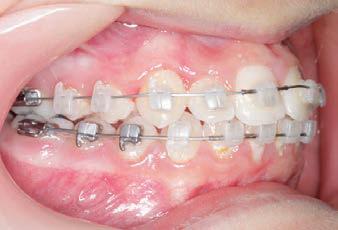

CLASS II DIV.1 - Marra

INITIAL - 4/4/18

PROGRESS 1 - 26/9/18 - Class I platform accomplished in 5.75 months with Motion 3D COLOR Appliance

PROGRESS 2 - 26/9/18 - Placement of the SLX 3D Clear Brackets